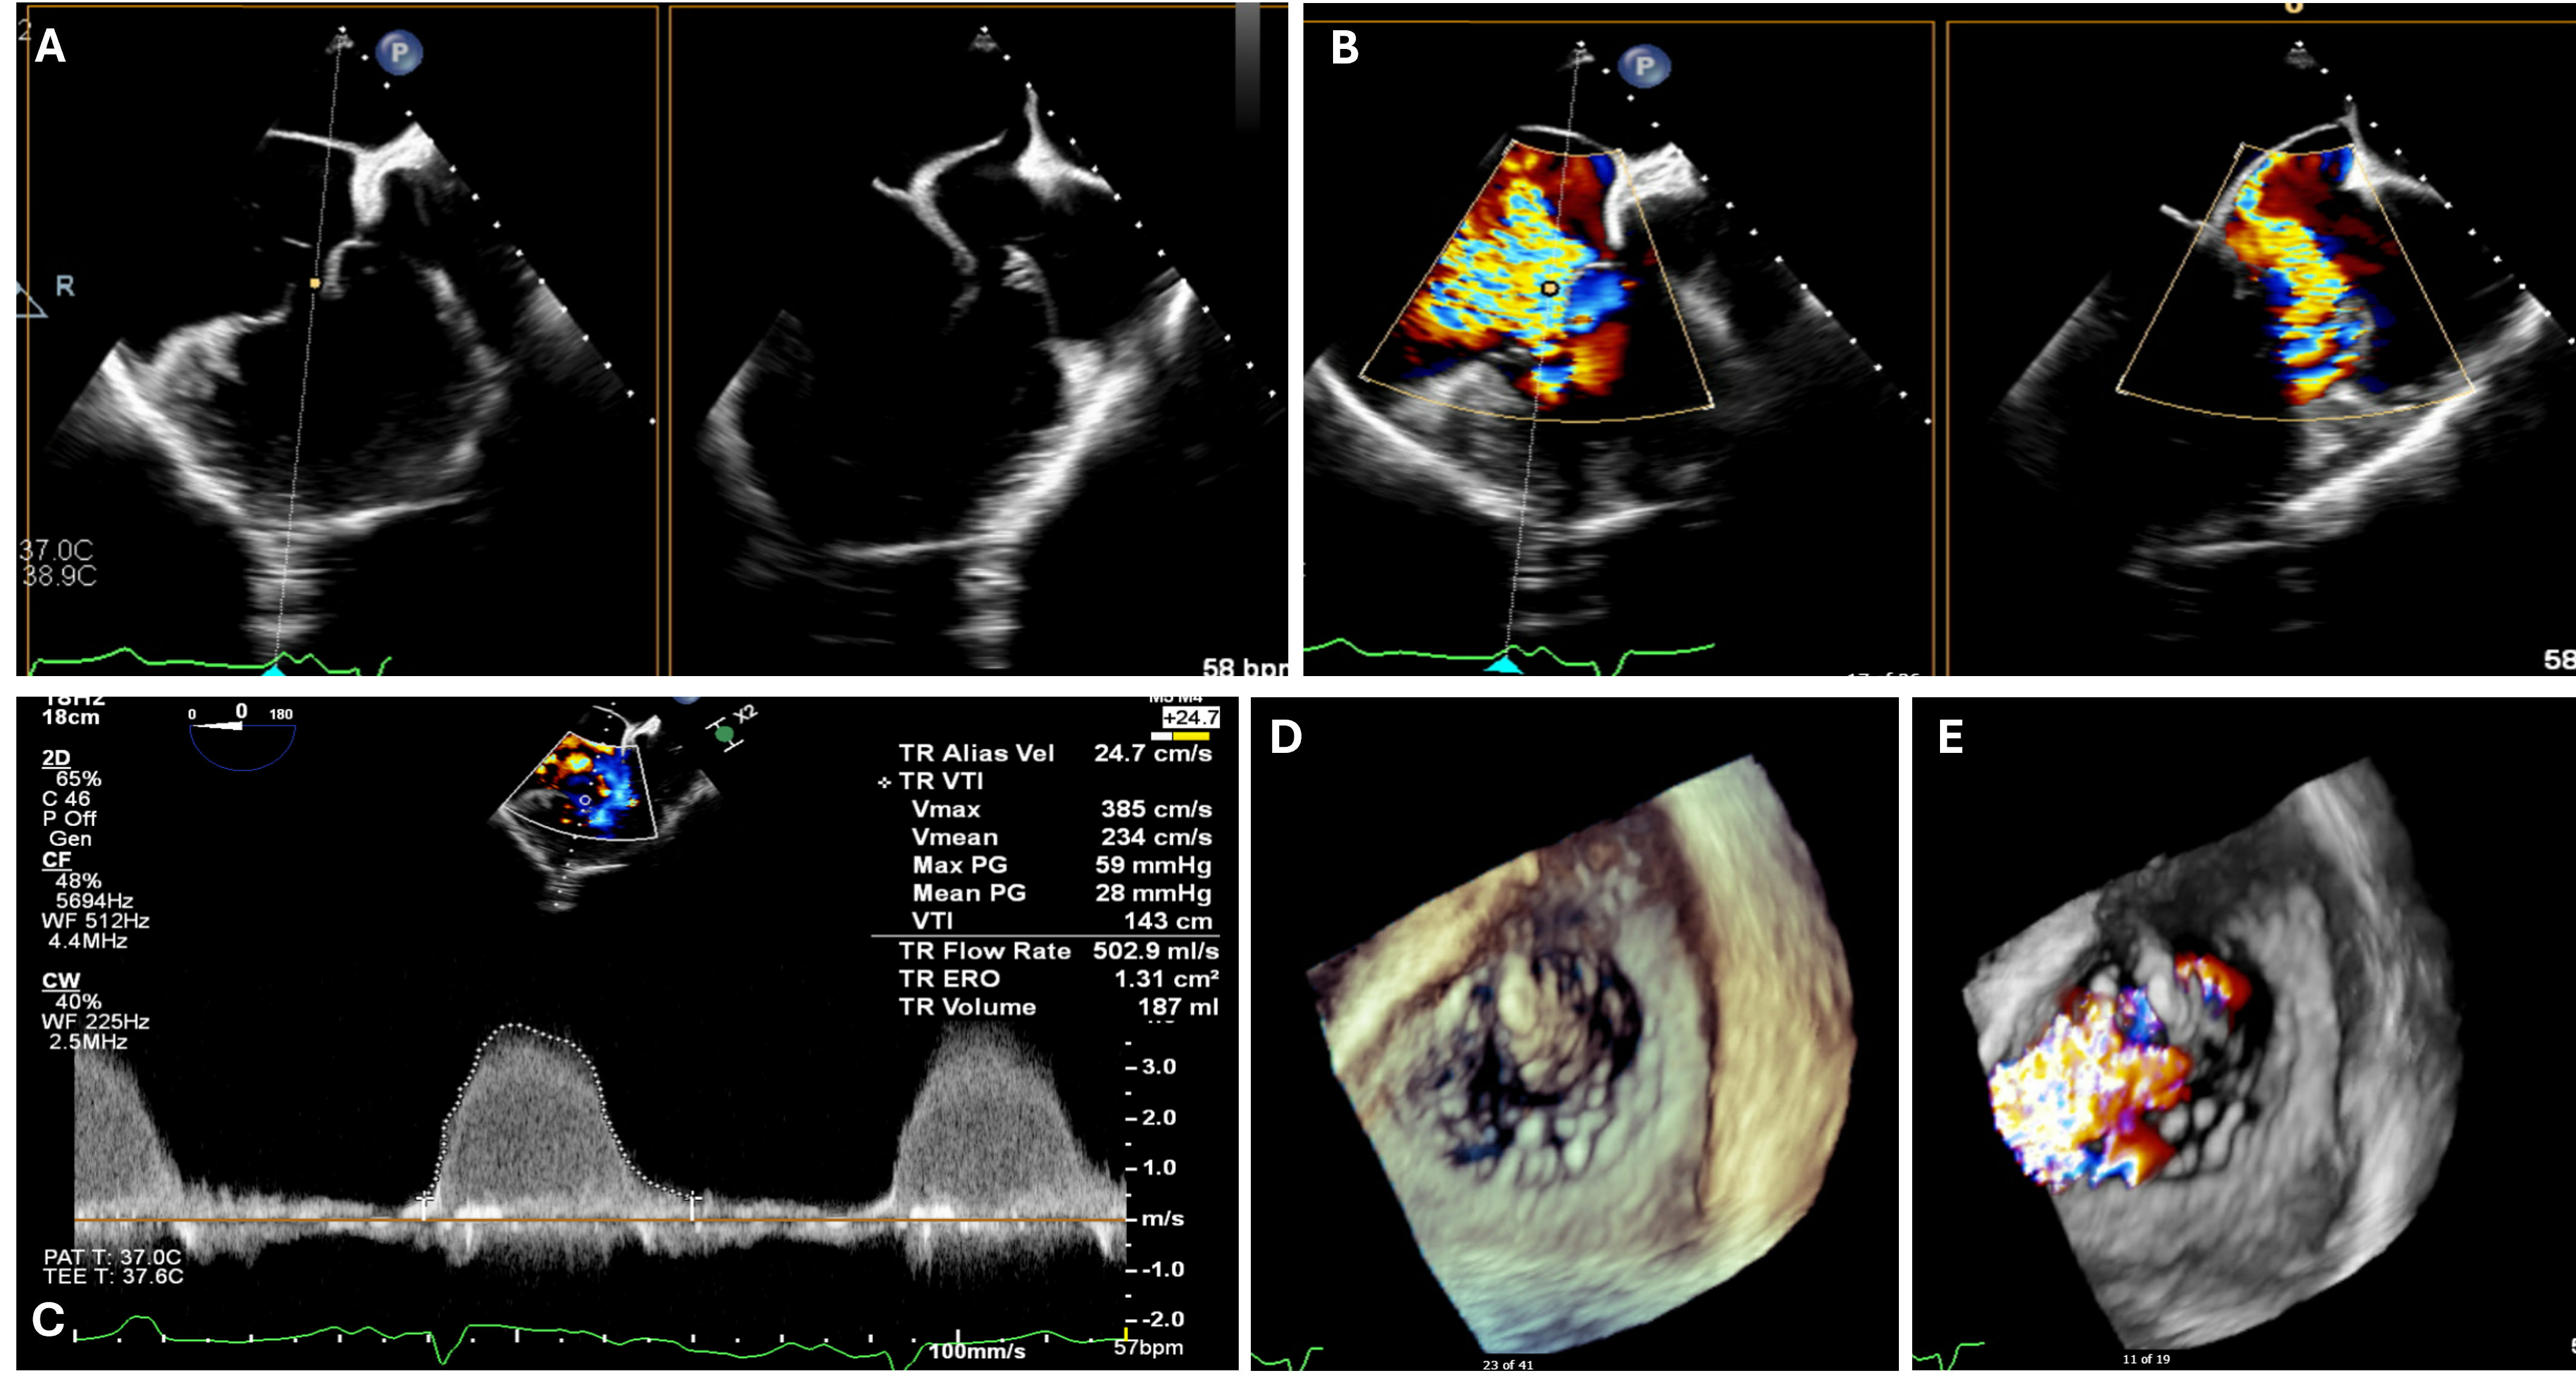

Computed tomography showed the inferior vena cava (IVC) draining into the right-sided right atrium and then into the target tricuspid valve, which is consistent with dextroversion of the heart (Figure 2A).

A TriClip G4 steerable guide catheter (Abbott) was advanced to the right atrium. The procedure was guided by both transesophageal echocardiography and intracardiac echocardiography (Figure 2B). The first TriClip XTW was positioned close to the anteroseptal commissure. The second TriClip XTW was deployed anteroseptally and slightly more to the center than the first clip. The third TriClip XTW was deployed in a similar manner even more centrally. Following these deployments, there was a significant reduction of tricuspid regurgitation (Figure 2C-E, Video 2). The final mean trans-tricuspid gradient was 2 mm Hg.